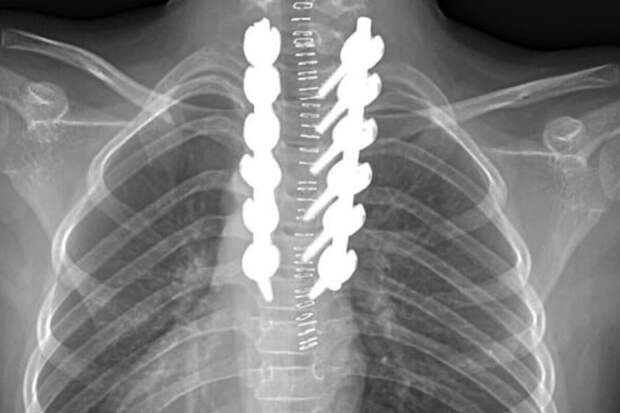

В России хотят создать адресную программу реанимации для получивших травмы позвоночника в зоне СВО бойцов. Об этом пишет "Коммерсантъ" со ссылкой на заявление зампреда Госдумы Анны Кузнецовой.

До этого российский врач перечислил главные ошибки при оказании первой помощи лицам с переломом позвоночника.